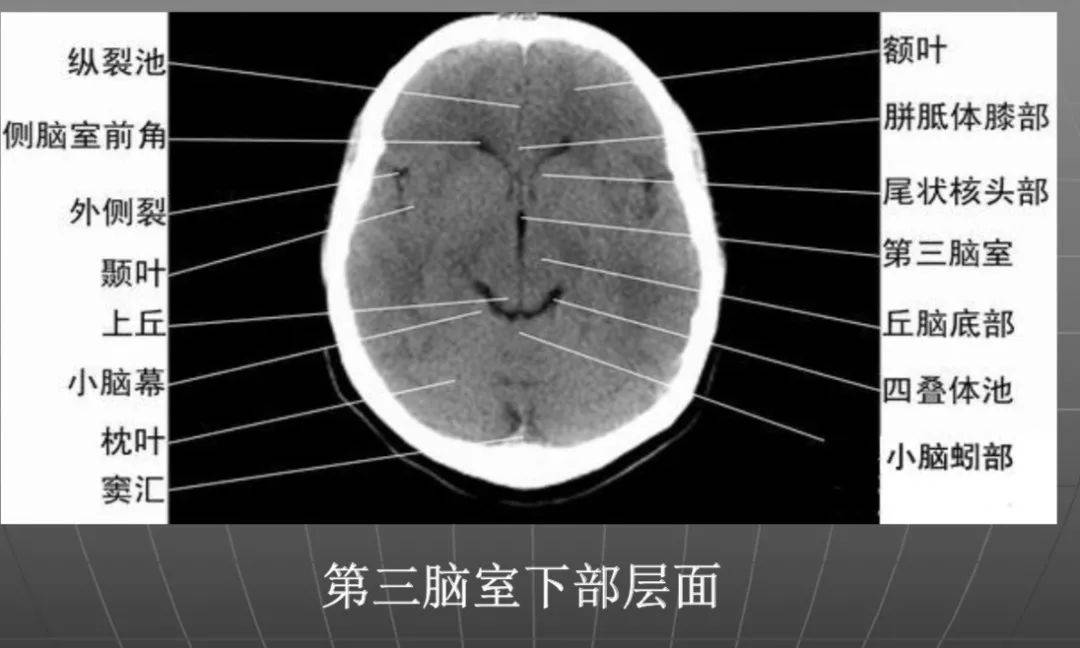

经第三脑室上部横断层ct

ct入门 | 颅脑ct精美解剖